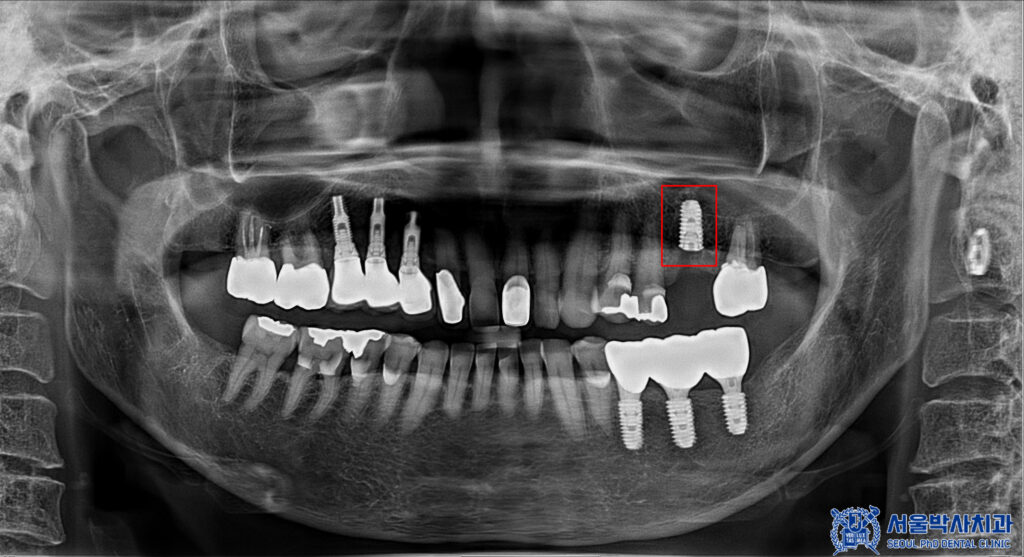

아래쪽의 보철이 마무리된 후,

발치했던 부분의

뼈이식을 포함한 무절개임플란트를

식립 하였습니다.

이때, 골다공증 주사제 시기 또한

본원에서 체크 및 조정하여

안정적으로 수술을 진행하였습니다.

치유기간을 기다린 후

위쪽도 본원 원내기공소에서

직접 제작한 개인 맞춤형

임플란트 보철물을

세팅해 드렸습니다.

마무리 후 사진입니다.

환자분께 골다공중 주사제 체크를 잘하여

안정적으로 임플란트 수술을

할 수 있게 도와드렸고

무절개임플란트 후

만족도가 매우 높으셨습니다.